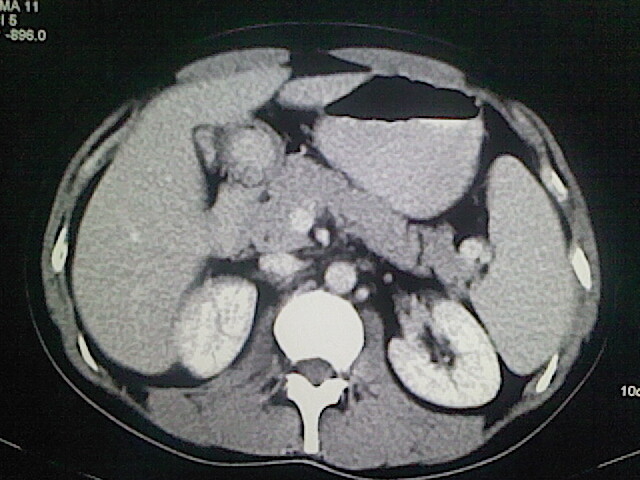

以下是引用卜一在2009-3-14 9:49:00的发言:[br]胆囊萎缩,胆囊壁不规则增厚,内部结构模糊,增强明显强化。另:肝左叶外侧段肝囊肿。支持:慢性胆囊炎!高度可疑:胆囊癌!

以下是引用余辉在2009-3-14 8:48:00的发言:[br]1)慢性胆囊炎。2)肝左叶外侧段肝囊肿。3)脂肪肝。[br]支持,胆囊萎缩,密度增高,不知b超具体有何提示,钙胆汁?结石?

以下是引用jiangjing在2009-3-14 10:18:00的发言:[br]1)慢性胆囊炎。2)肝左叶外侧段肝囊肿。3)脂肪肝。4.】建议行肝功能检查